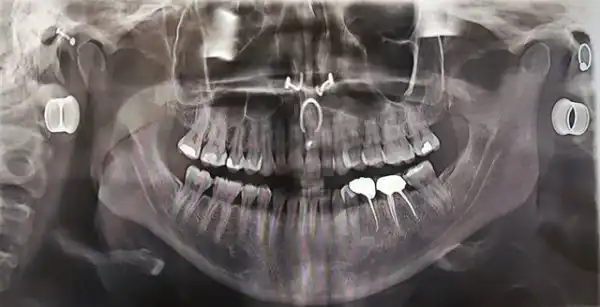

У меня есть зуб на подбородке